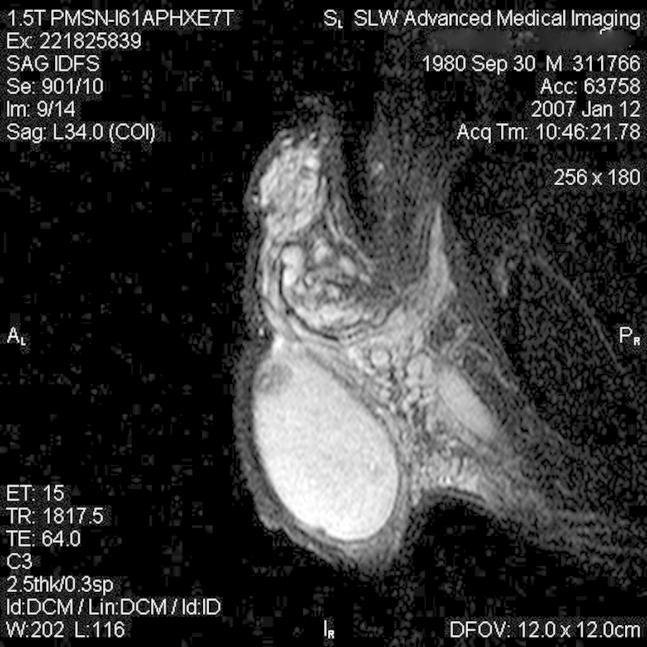

The diagnosis of a testicular sclerosing Sertoli cell tumor is rare. Approximately 17 cases have been previously described in the literature worldwide. We present a case and review the evaluation and surgical management of a sclerosing Sertoli cell tumor presenting in a 26 year-old African-American adult, in association with testicular microlithiasis and oligospermia. Imaging techniques and the pathological assessment will be reviewed.

睾丸硬化性支持细胞瘤的诊断较为罕见。此前全球文献中大约已报道过17例。我们报告1例病例,并回顾1例26岁非裔美国成年男性患者的硬化性支持细胞瘤的评估及外科治疗情况,该病例伴有睾丸微结石症和少精子症。我们还将回顾影像技术及病理评估情况。